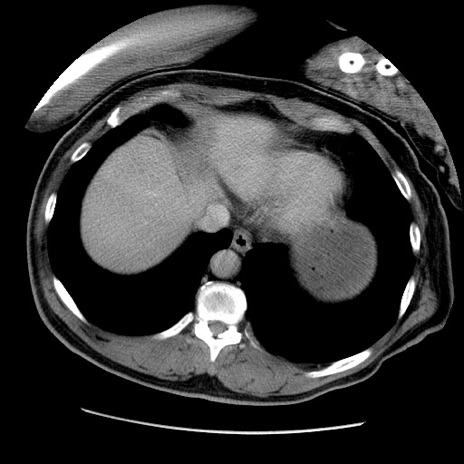

症例22(横断像)

【症例】50歳代男性

【主訴】腹痛

【現病歴】AVMからの被殻出血のため回復期リハ病棟入院中。 本日午後3時頃急に下腹部痛が出現した。

【既往歴】AVM、被殻出血、虫垂炎、高血圧

【身体所見】意識晴明、左半身不全麻痺、会話の理解は良好、36.5°C、腹部:膨隆、全体に板状硬、下腹部正中に圧痛点あり、反跳痛-、筋性防御不明、右下腹部にope scar

【データ】WBC 9400、CRP 0.06